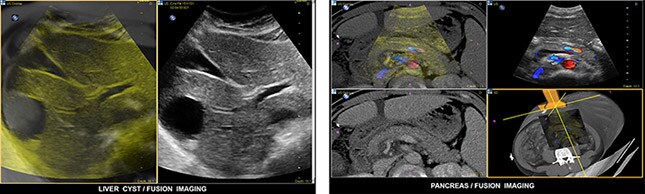

The image above shows a fusion image of a liver cyst (left) and a fusion image of a pancreas (right) using PercuNav. Images courtesy of Dr. Clevert.